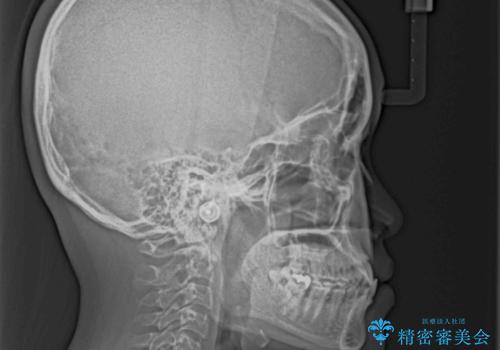

- 全顎的なクロスバイトと反対咬合を気にして来院された患者様です。

骨格的に下顎が前方位にありましたが、歯並びにより下顎が本来の位置よりも前方位に誘導される咬み合わせとなっていました。

上顎歯列および上顎骨が下顎に対して狭小であることが原因であるため、上顎の急速拡大装置を使用して上顎骨を側方に拡大することで反対咬合を改善し、ワイヤー装置で歯列を整えることとしました。